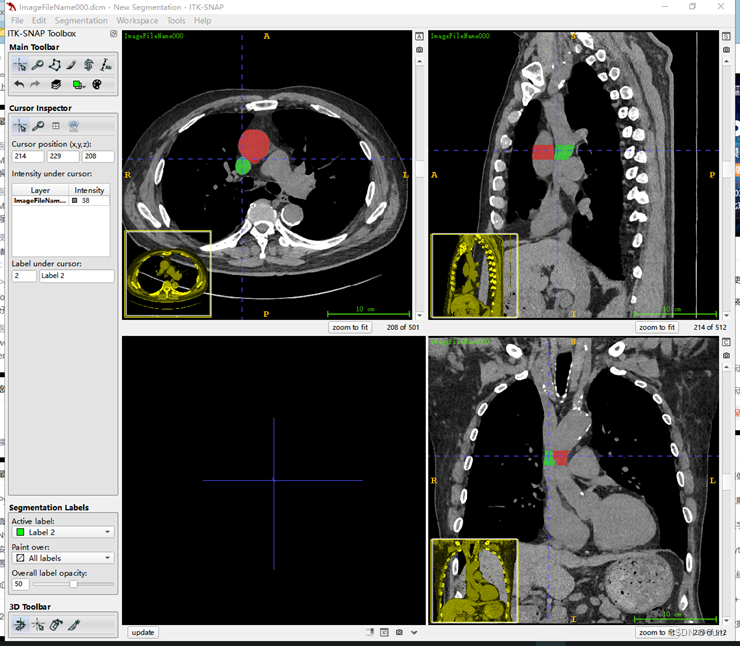

4 数据标注

画面大小可以通过按住鼠标右键拖动进行调整,左键调整画面位置。

标注方法一:套索标注

套索标注有两个选项,Smooth和Polygon,推荐选用Smooth来进行拖动鼠标画取消,Polygon为给定关键点生成折线比较糙一些。画好外圈轮廓之后点击回车即可生成标注。选用一个方向的轴向图标注即可。

根据上图,选择好标注工具后,通过切换切片一张一张地进行标注(也可以通过滚动鼠标来切换),使用套索标注的例子(下面是放大之后的效果):

标注过程中,有两种方式,一种是通过长按鼠标左键进行标注;一种是通过不断单击鼠标左键进行标注。(具体感受一下就知道了)

对不同部位使用不同的标签,点击上图中的圈出位置,进行切换标签(颜色不同)。标注之后的效果如下:

为了方便标注,可以点击上图圈出的位置放大这个方向上的轴向图。效果如下

在这里我连续标注了多张,只选择了两个区域,相当于用了两种标签,效果如下

容易发现三个方向的图都有对应的标签。通过点击下图圈出的update会生成3D的标签图: